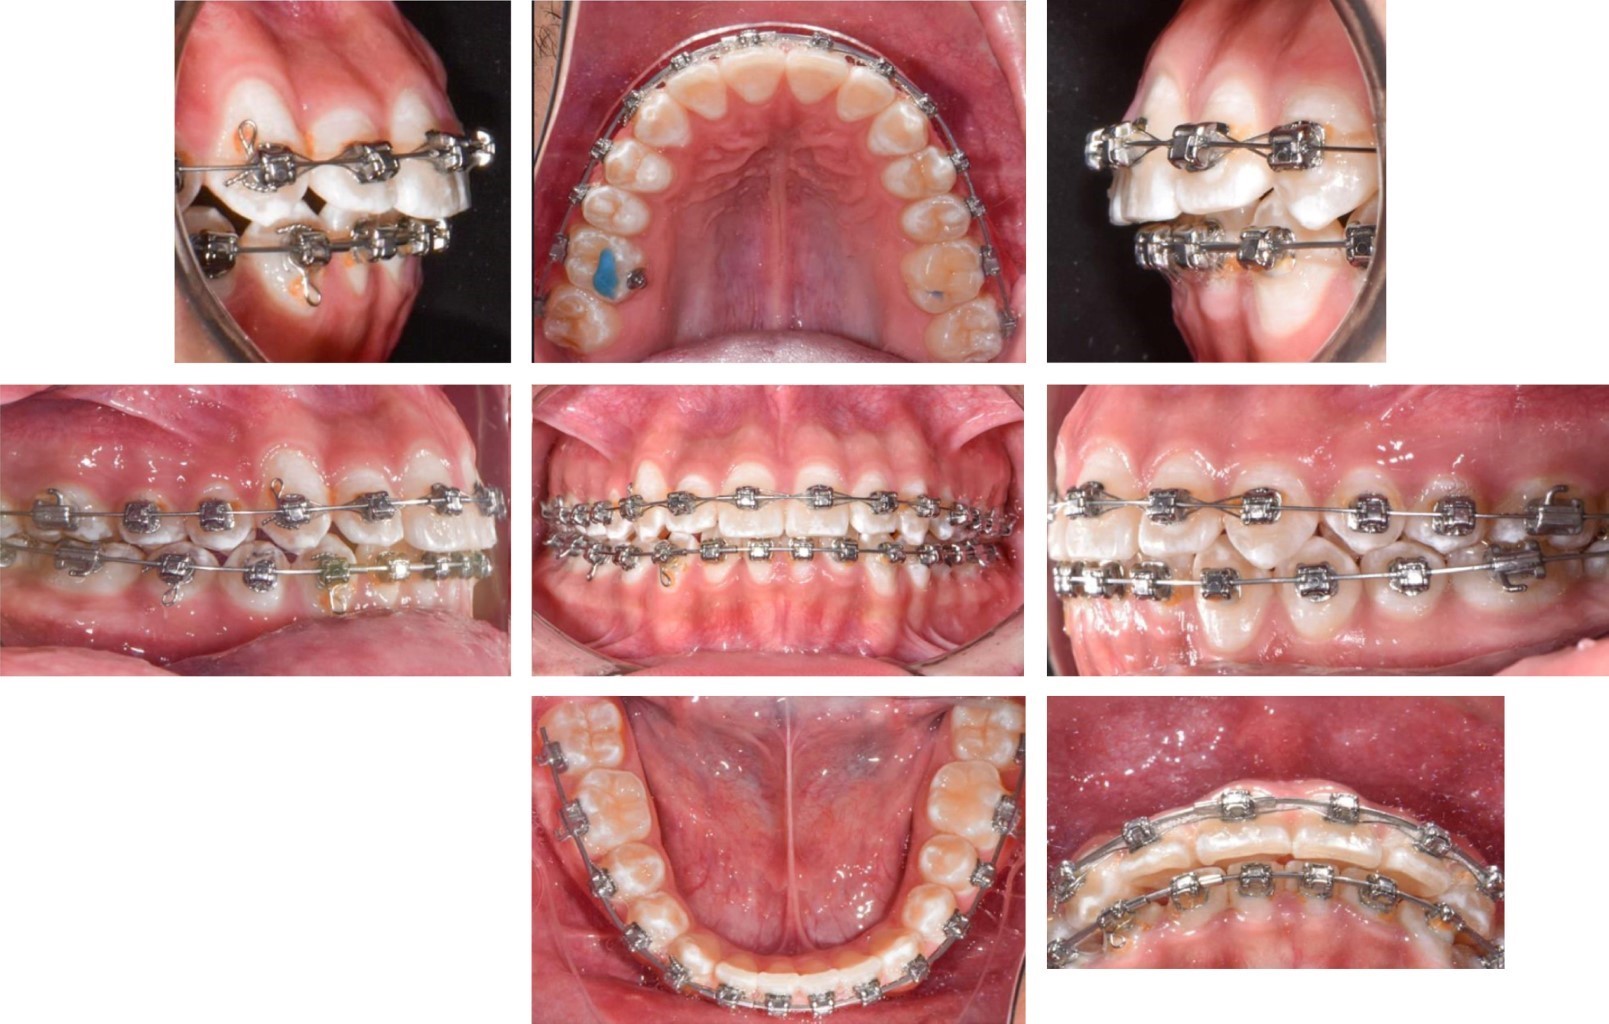

Paciente de género masculino de 13 años 10 meses de edad, sin antecedentes médicos relevantes, que acudió a la clínica de ortodoncia con motivo de consulta "quiero acomodar mi diente". En el análisis extraoral, el paciente presentó un perfil recto, biotipo dolicofacial incipiente, tercio inferior aumentado, pómulos sin proyección (Figura 1A). En la exploración intraoral el paciente mostró dentición permanente, clase II molar derecha, clase II canina derecha y clase I izquierda, forma de arco superior e inferior triangular, dientes grandes y cuadrados, línea media superior desviada 2 mm a la derecha, sobremordida horizontal 3 mm, sobremordida vertical 2 mm (Figura 1B). En el análisis de modelos en el estudio de Bolton presentó exceso maxilar de 3.2 mm, discrepancia de longitud de arco -6 mm superior y -2 mm inferior, con apiñamiento severo anterior superior (Figura 2).

Posteriormente se incorporó el canino al arco y se colocó un arco 0.014" CuNiTi. Una vez incorporado a la arcada, se pasó a un arco 0.018" CuNiTi y se continuó con el uso de elásticos vector clase II ligeros de ¼ 2.5 oz. Tres meses después se colocó un arco 0.014" × 0.025" CuNiTi superior y 0.018" CuNiTi inferior (tres meses). A continuación, se cambió a un arco 0.018" × 0.025" CuNiTi superior e inferior y se colocó un botón en el primer molar superior derecho para el uso de elástico cruzado al primer molar inferior derecho de 3/16 4.5 oz (Figura 5). Después de tres meses se retiraron los bite turbos y se colocaron arcos 0.018" × 0.025" de acero superior e inferior (Figura 6). Por último, se retiró la aparatología y se colocó un retenedor fijo inferior y retenedor tipo essix superior.